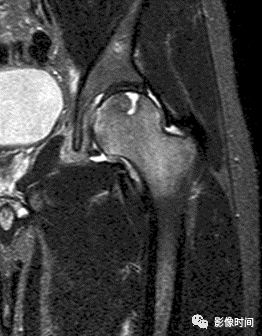

四、肿瘤内液-液平面

肿瘤内液-液平面多数是病灶内囊变出血所致,MRI T2W1 为上部呈高信号下部呈中低信号的液-液平面。CT 可为上部低密度下部高密度的液-液平面(图 32)。液-液平面常见于动脉瘤样骨囊肿、但也可见于骨内腱鞘囊肿(图 33)、囊性血管瘤病等其他肿瘤和肿瘤样病变。

图 32 肿瘤内液-液平面:动脉瘤样骨囊肿

图 33  肿瘤内液-液平面:动脉瘤样骨囊肿

图 34  肿瘤内液-液平面:骨内腱鞘囊肿